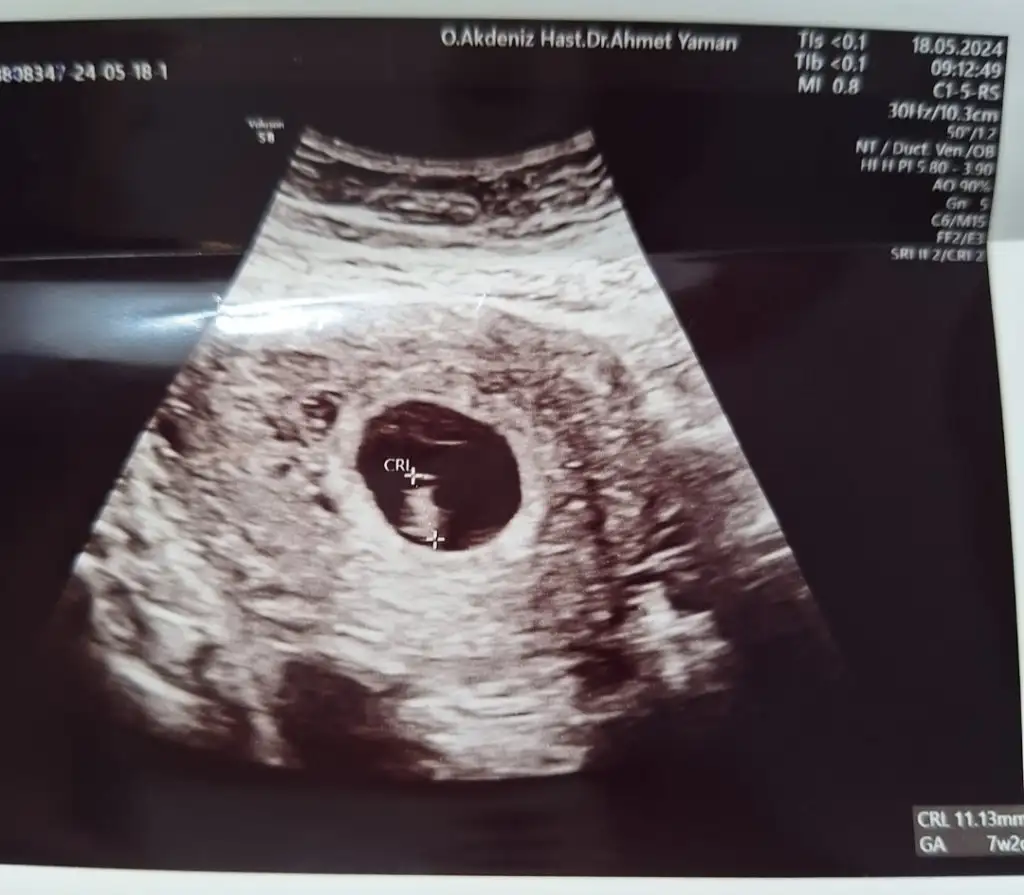

Kızlar benim de randevum pazartesi son adet tarihine göre bugün 6+2 deyim.Heyecanlıyım kese görülecek mi kalp atışı duyulacak mı zaman geçmiyor

Benim de randevum pazartesi ben gittiğimde sat a göre 5+3 olacağım. Kese kesin görülür. Eğer vajinal bakarlarsa belki sen kalp atışını da duyabilirsin

Oyy yerim maşallah benim de 7+2 aynı zamanlarda kucağımıza alacağız inşallah cinsiyetleri de öğrenelim hayırlısıyla